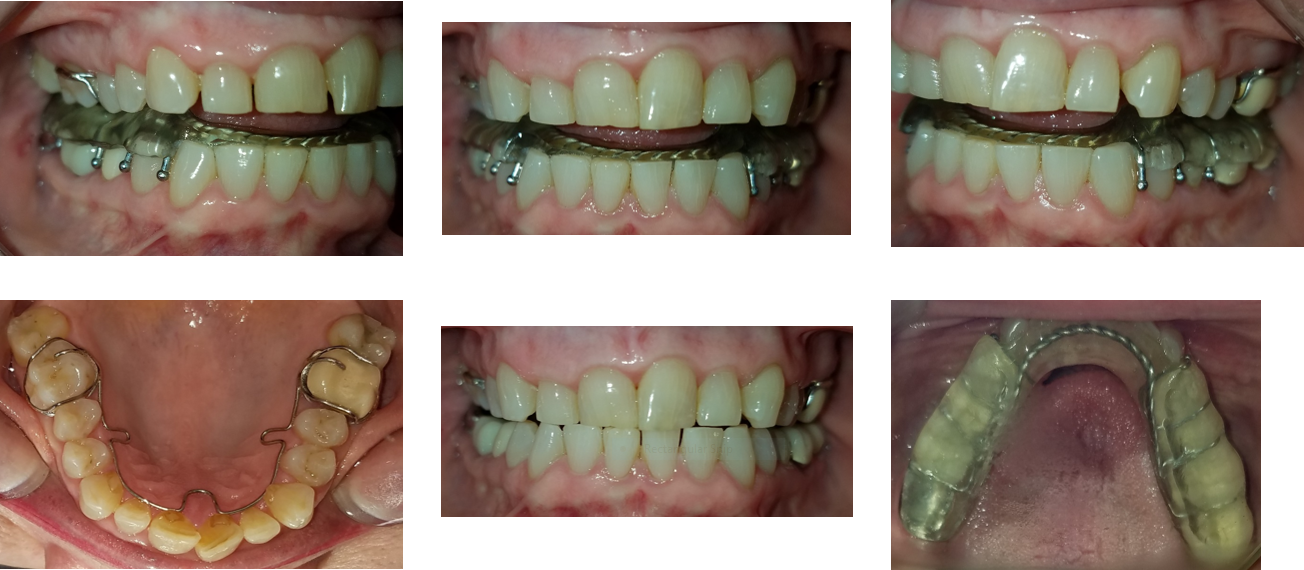

Initial cone beam computed tomography (CBCT) revealed low tongue posture (Figure 1). Figures 2, 3, and 4 show the frontal, maxillary occlusal, and mandibular occlusal views of the dentition, respectively. Clinical examination identified a scalloped tongue with low muscle tone and difficulty achieving palatal suction. Dental findings included upper and lower arch crowding, advanced tooth wear consistent with attrition, a deep skeletal bite evident on cephalometric analysis, and a marked loss of vertical dimension of occlusion (VDO) (Figures 5 and 6).

Figure 2.

(more ...)

Figure 3.

Figure 4.